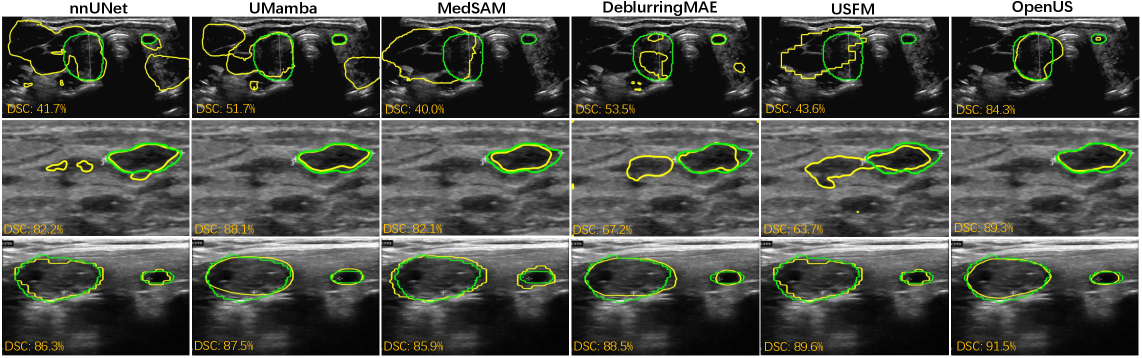

Refer to caption

Figure 4: Visualization of US segmentation results on TN3K and BUS-BRA. The ground truth is depicted in green, and the prediction is shown in yellow.

We visualize segmentation results in Fig. 4. Clearly, OpenUS outperforms other methods in accurately recognizing hazy tissue borders and demonstrates greater robustness to speckle in US images. Specifically, OpenUS demonstrates superior visual results in segmenting both large and small thyroid nodule regions (1st1^{st} rows in Fig. 4). We attribute these improvements to our self-adaptive masking strategy, which effectively captures more precise and clinically relevant details from US images. Similarly, OpenUS also exhibits strong performance in segmenting breast tumour (2nd2^{nd} row in Fig. 4).

Figure 9: Visualization of US segmentation results on TN3K and BUS-BRA. The ground truth is depicted in green, and the prediction is shown in yellow.

Fig. 9 demonstrates the segmentation results of our method and other superivised and self-supervised pre-training methods on the TN3K and BUS-BRA datasets. The results indicate that OpenUS outperforms other methods in the accurate recognition of indistinct tissue borders and demonstrates greater robustness to speckle noise in US images. Specifically, for thyroid nodule segmentation tasks involving noisy, low-quality US images (1st1^{st} and 3rd3^{rd} row in Fig. 9), nnUNet, UMamba, MedSAM, DeblurringMAE, and USFM inaccurately segment artefacts, whereas OpenUS remains robust. While some small thyroid nodules occupy very few pixels and are prone to omission (1st1^{st} row in Fig. 9), OpenUS successfully segments these challenging structures. In the breast cancer segmentation task (2nd2^{nd} row, Fig. 9), our method produces segmentation masks with smoother and more continuous edges. In contrast, other methods often yield results corrupted by speckle noise or containing inaccurate lesion boundaries.